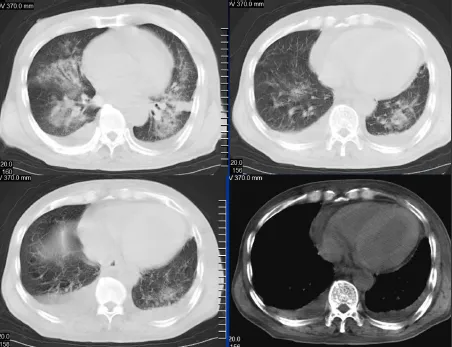

CT表现:

①心脏增大;

②肺淤血:CT表现为肺门影增大,支气管血管束增多增粗,密度增高,边缘模糊,肺野密度增高,出现磨玻璃样高密度影。

③肺间质水肿:CT表现为两肺纹理增粗模糊,呈毛玻璃样改变,以双上肺明显,并见Kerley线;

④肺泡样肺水肿:CT表现为两肺透光度减低,并见广泛性分布结节样、斑片样密度增高影及毛玻璃样影,边缘模糊,以两肺内、中带分布较明显,形成典型“蝶翼征”;

⑤胸腔积液。